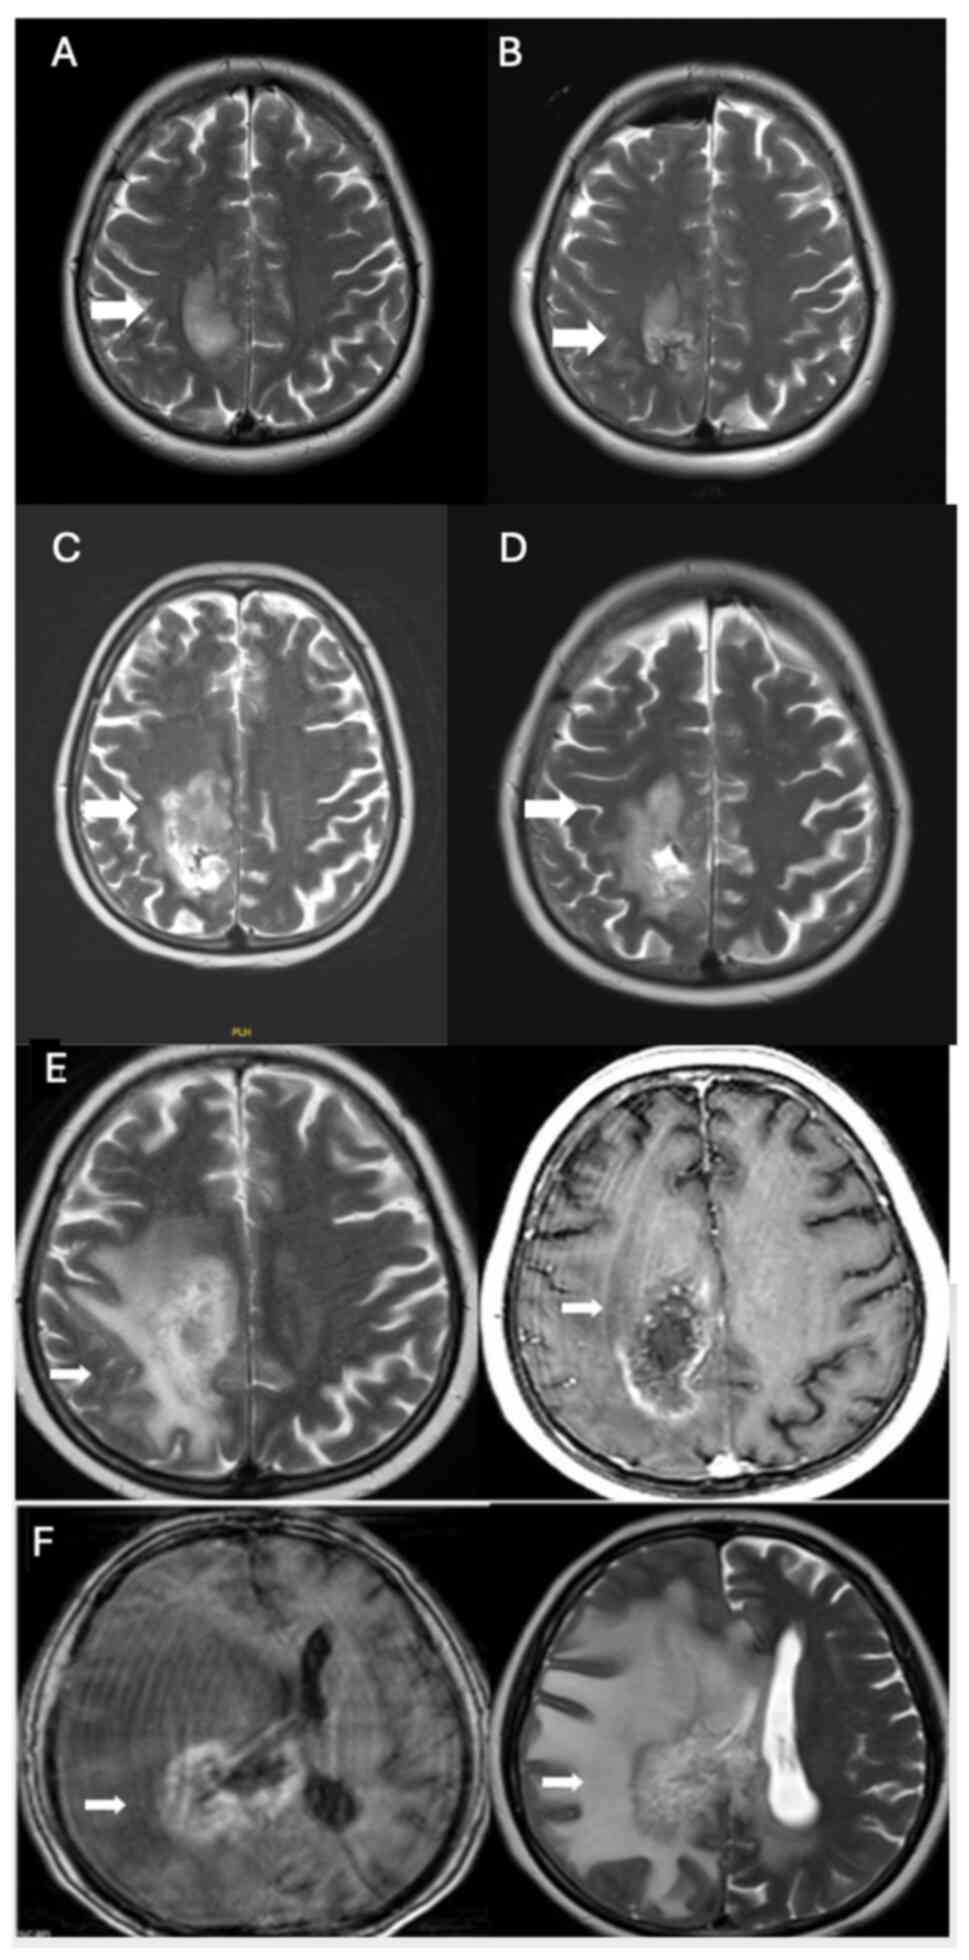

In January 2021, an intracranial mass was detected (Fig. 3A) and operated in a 45-year-old male patient (Fig. 3B) at The Department of Neurosurgery, Hacettepe University Faculty of Medicine, resulting in the diagnosis of glioblastoma, IDH wild-type, WHO grade IV. Immunohistochemical analysis was performed on paraffin-embedded tissue samples using primary antibodies against GFAP, Ki67, IDH1, p53 and ATRX. GFAP staining was positive and ATRX expression was maintained. IDH1 (R132H) staining was negative. The Ki-67 proliferation index was ~30% and p53 was overexpressed in 30% of the tumor cells. Concurrent chemoradiotherapy with temozolomide treatment was initiated for the patient; however, temozolomide treatment had to be discontinued due to the side effects of prolonged thrombocytopenia and neutropenia. Following radiotherapy, adjuvant bevacizumab-irinotecan treatment was started in April 2021. After six cycles of treatment, there was a minimal reduction in tumor size, accompanied by a decrease in contrast enhancement (Fig. 3C).

Figure 3.

(A) Tumor infiltration into the corpus callosum splenium and protrusion into the intraventricular space, along with involvement of the fornixes, was evident in January 2021 (white arrows). (B) Postoperative MRI confirming GBM diagnosis after surgery (white arrow). (C) GBM showed a slight reduction in size during the interval period (measurements captured at the level of the right part of the corpus callosum splenium and anterior commissure; white arrows). Additionally, there was a decrease in gross contrast enhancement compared with the lesion, which had increased in size and diffusely infiltrated the corpus callosum splenium in March 2021. (D) Increased heterogeneity, minimal shrinkage in the corpus callosum corpus posterior isthmus and splenium part, and prominent necrotic parenchymal changes, particularly on the right, were observed in April 2022 (white arrows). A focal area suggested tumoral infiltration, especially in the presence of bevacizumab, although it did not exhibit increased cerebral blood volume values (not shown). This infiltration extended to the posterior part of the right lateral ventricular corpus and the corona radiata. (E) MRI following three cycles of pembrolizumab and Cyberknife treatment in June 2022, showing stable disease surrounding the posterior part of the right lateral ventricle (white arrow). MRI, magnetic resonance imaging; GBM, glioblastoma multiforme.

The patient began to experience numbness in their arms and legs ~10 months into the treatment. In April 2022, a cranial MRI revealed progressive disease (Fig. 3D), prompting the initiation of pembrolizumab treatment at a dosage of 200 mg every 3 weeks and the administration of cyberknife treatment in June 2022. Following three cycles of treatment, the tumor remained stable, surrounding the posterior part of the right lateral ventricle (Fig. 3E).

In October 2022, mild compression fractures on the upper articular surfaces of the L2-S1 vertebral corpuscles were detected, leading to vertebroplasty being performed in the Department of Orthopedics at Hacettepe University Faculty of Medicine. In November 2022, the patient was admitted to the emergency room with loss of consciousness, and after a 2-month stay in the Neurosurgical Intensive Care Unit at Hacettepe University Faculty of Medicine, the patient died in January 2023.